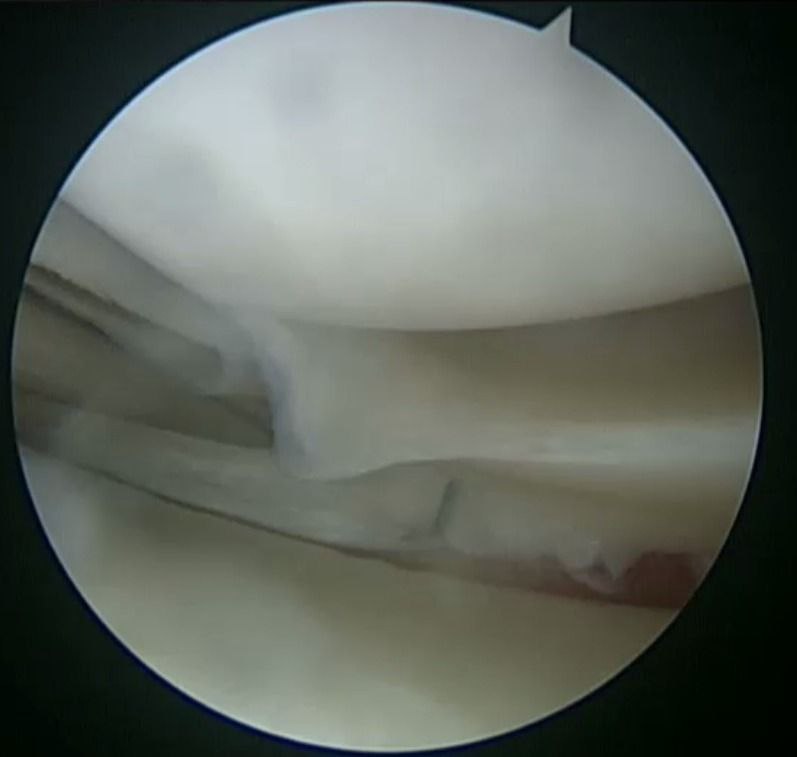

Наложения артроскопического шва заднего рога медиального мениска

По итогам исследования и определения диагноза пациенту был предложен и реализован план лечения: предоперационная реабилитация и проведение операции по поводу наложения артроскопического шва заднего рога медиального мениска, а также проведена пластика передней крестообразной связки сухожилием полусухожильной и тонкой мышц правого коленного сустава.